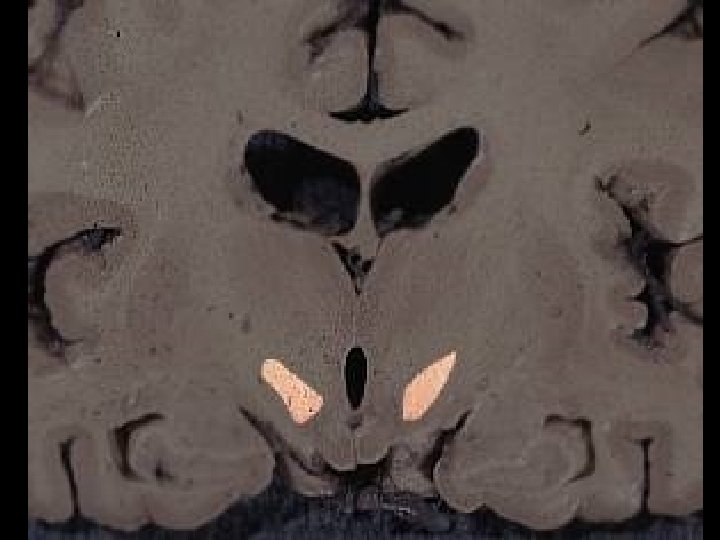

Thalamus (thalamus dorsalis) • • • „sekretářka mozku“ vše kromě čichu pulvinar (dorzálně) tuberculum anterius (ventrálně) lamina medullaris medialis + lateralis thalami adhesio interthalamica (80 %) – bez významu jádra se rozdělují se podle polohy nebo zapojení – nuclei anteriores, dorsales, intralaminares, mediani, mediales, posteriores, ventrales, reticularis – specifická senzorická jádra – specifická nesenzorická jádra – nespecifická jádra – asociační jádra

Třídění thalamických jader dle polohy nuclei anteriores, dorsales, intralaminares, mediani, mediales, posteriores, ventrales, reticularis